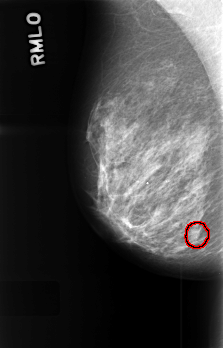

C_0420_1.RIGHT_MLO

RIGHT_MLO LINES 4520 PIXELS_PER_LINE 2888 BITS_PER_PIXEL 12 RESOLUTION 50 OVERLAY

FILE: C_0420_1.RIGHT_MLO.OVERLAY

TOTAL_ABNORMALITIES 1

ABNORMALITY 1

LESION_TYPE MASS SHAPE LOBULATED MARGINS MICROLOBULATED

ASSESSMENT 3

SUBTLETY 3

PATHOLOGY BENIGN_WITHOUT_CALLBACK

TOTAL_OUTLINES 1

BOUNDARY